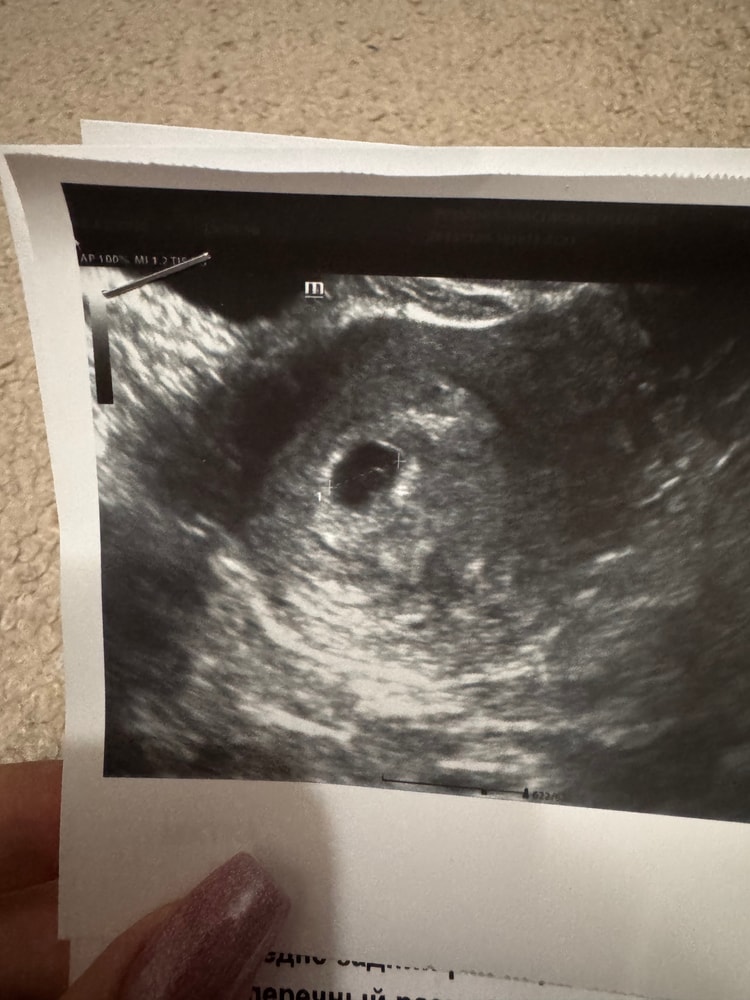

узи в 5+6

УЗИ

овуляция поздняя (18-19дц)

плодное яйцо 7.6 мм

желточный мешочек 3.2 мм